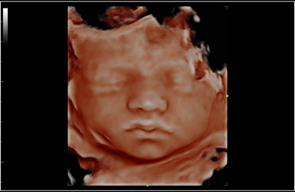

The birth of a new baby is an exciting time for parents, family and friends! At Bonding Moments, we offer a warm family atmosphere that offers Elective 2D/3D/4D and HD prenatal ultrasounds. We use state of the art ultrasound technology that allows our trained technicians to bring your baby to life before your very eyes on an 86 in flat screen TV surrounded by up to 12 of your guests. The realistic images will provide a bonding experience between mommy, daddy, family and friends. See baby yawn, hiccup, smile and kick all in real-time. So, let’s take a journey together and peek inside your baby’s world!

A prenatal ultrasound uses a transducer to deliver high frequency sound waves. Echoes of the sound waves are recorded and transformed into pictures. A gel is applied to the belly and transducer before the scan which helps conduct the sound waves. 2D and 3D are still images .4D adds motion and dimension so it looks like a video and HD adds more realism.